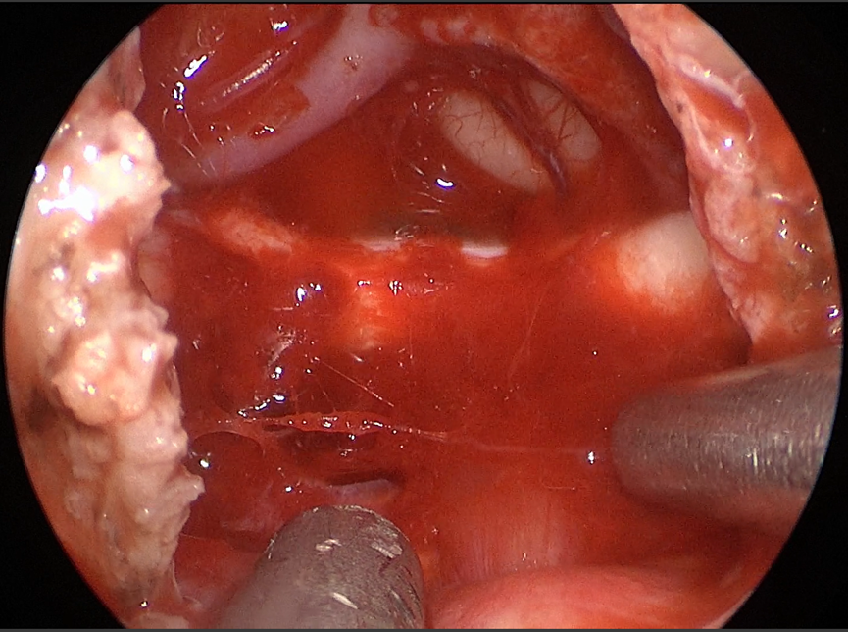

自近蝶窦前壁处向左侧推挤鼻中隔,离断筛骨垂直板,咬除部分近蝶窦处骨性鼻中隔,分离双侧鼻粘膜显露蝶窦前壁,自蝶窦开口上方做沿鼻中隔做粘膜瓣备用,末端到中鼻甲位置,将粘膜瓣压向下鼻道,高速磨钻磨除蝶窦下壁骨质,鞍结节骨质。术中视神经管清晰可见,给予保护,海绵间窦出血给予流体明胶+凝血酶止血;等离子刀一边止血一边切开硬脑膜见白色肿瘤质韧,边界清晰,大脑前动脉分支粘连于肿瘤表面,给予小心分离,以刮圈,咬切钳等小心清除肿瘤组织;内镜下将肿瘤完整切除;取右侧大腿皮下脂肪及阔筋膜备用,以人工硬膜修补和明胶海绵封闭鞍底硬膜,将脂肪放置于切口,并缝合于鞍底硬脑膜上固定铺平,阔筋膜覆盖于脂肪外边,蝶窦内充填明胶海绵止血,鼻粘膜瓣覆盖于蝶窦;碘仿纱条填塞鼻腔;护士清点棉条、器械、纱布无误,撤出鼻镜。